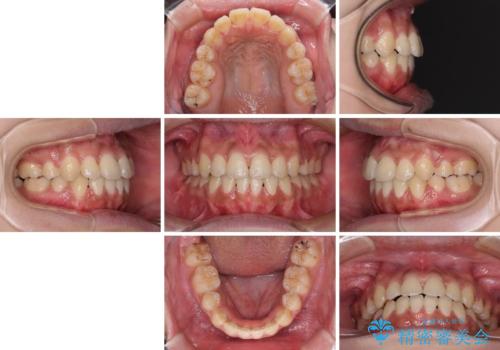

- 八重歯と上下前歯のでこぼこを気にして来院された患者様です。

上下前歯部叢生のスペース獲得のため、上下顎左右小臼歯各1歯(計4本)と全ての親知らずを抜歯して、矯正治療を行うこととしました。

上下の正中位置が大きくずれていたため、治療期間の長期化や正中が合わないまま終了することが予想されましたが、思っていた以上にスムーズに歯が移動し、満足いただける仕上がりとなりました。